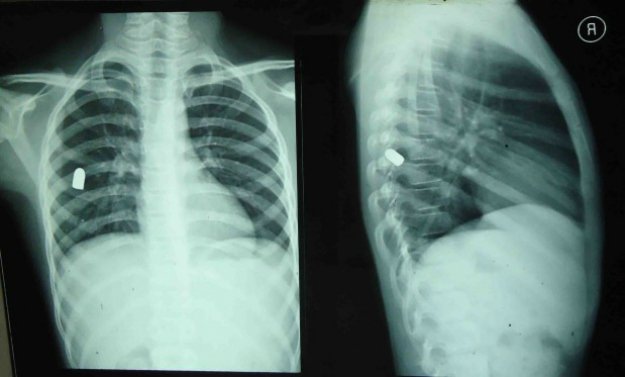

同样,如果*弹子**击中人体躯干,比如胸腹部这些部位,这个绝对就是要命的了,特别是被*弹子**击中后*弹子**没有穿透,而是停留在人体内部,这种情况下就看这个被击中者的运气了,比如*弹子**击中脏器,但是没有直接切断脏器内部血管,比如肺部中弹,但是仅仅击穿肺叶,而没有击穿里面的血管,胃部中弹,肠道中弹等,但是这里并不是说这些伤没事,这些伤是重伤,而且是很危险的,受创的器官会因为失血等失去应有功能导致其他脏器失效,直接导致人体死亡。

同时*弹子**进入人体后,并不会一个方向,或者是整体不变形,*弹子**往往会碎裂,会在身体内走不规律的路线,从而导致多器官受损,直接导致多器官衰竭。因此一旦*弹子**击中躯干部位,那就只要看你是不是运气好了,我们曾经看到过一个被警用*弹子**连续击中四枪的犯罪嫌疑人,其中一颗击中左臀部的*弹子**竟然从他的右后背腰部以上飞出,而击中右前胸的一颗*弹子**居然从左臂内测飞出同时切断了左臂内存动脉血管,尽管EMS在第一时间就到达,而且带了很多血浆和快速输血器材,但是嫌疑人还是在不到两分钟内就死亡了,这种枪伤其实也基本是没有任何希望的,只不过是早点晚点死亡而已。